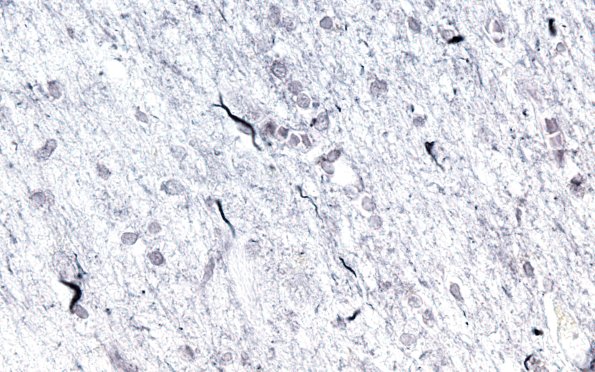

Washington University Experience | NEURODEGENERATION | Argyrophilic Grain Disease (AGD) | 3C5 Argyrophilic Grain Dementia (Case 3) L23 Gallyas 60X WM 4

These oligodendroglial inclusions are often called coiled bodies. (Gallyas stain)